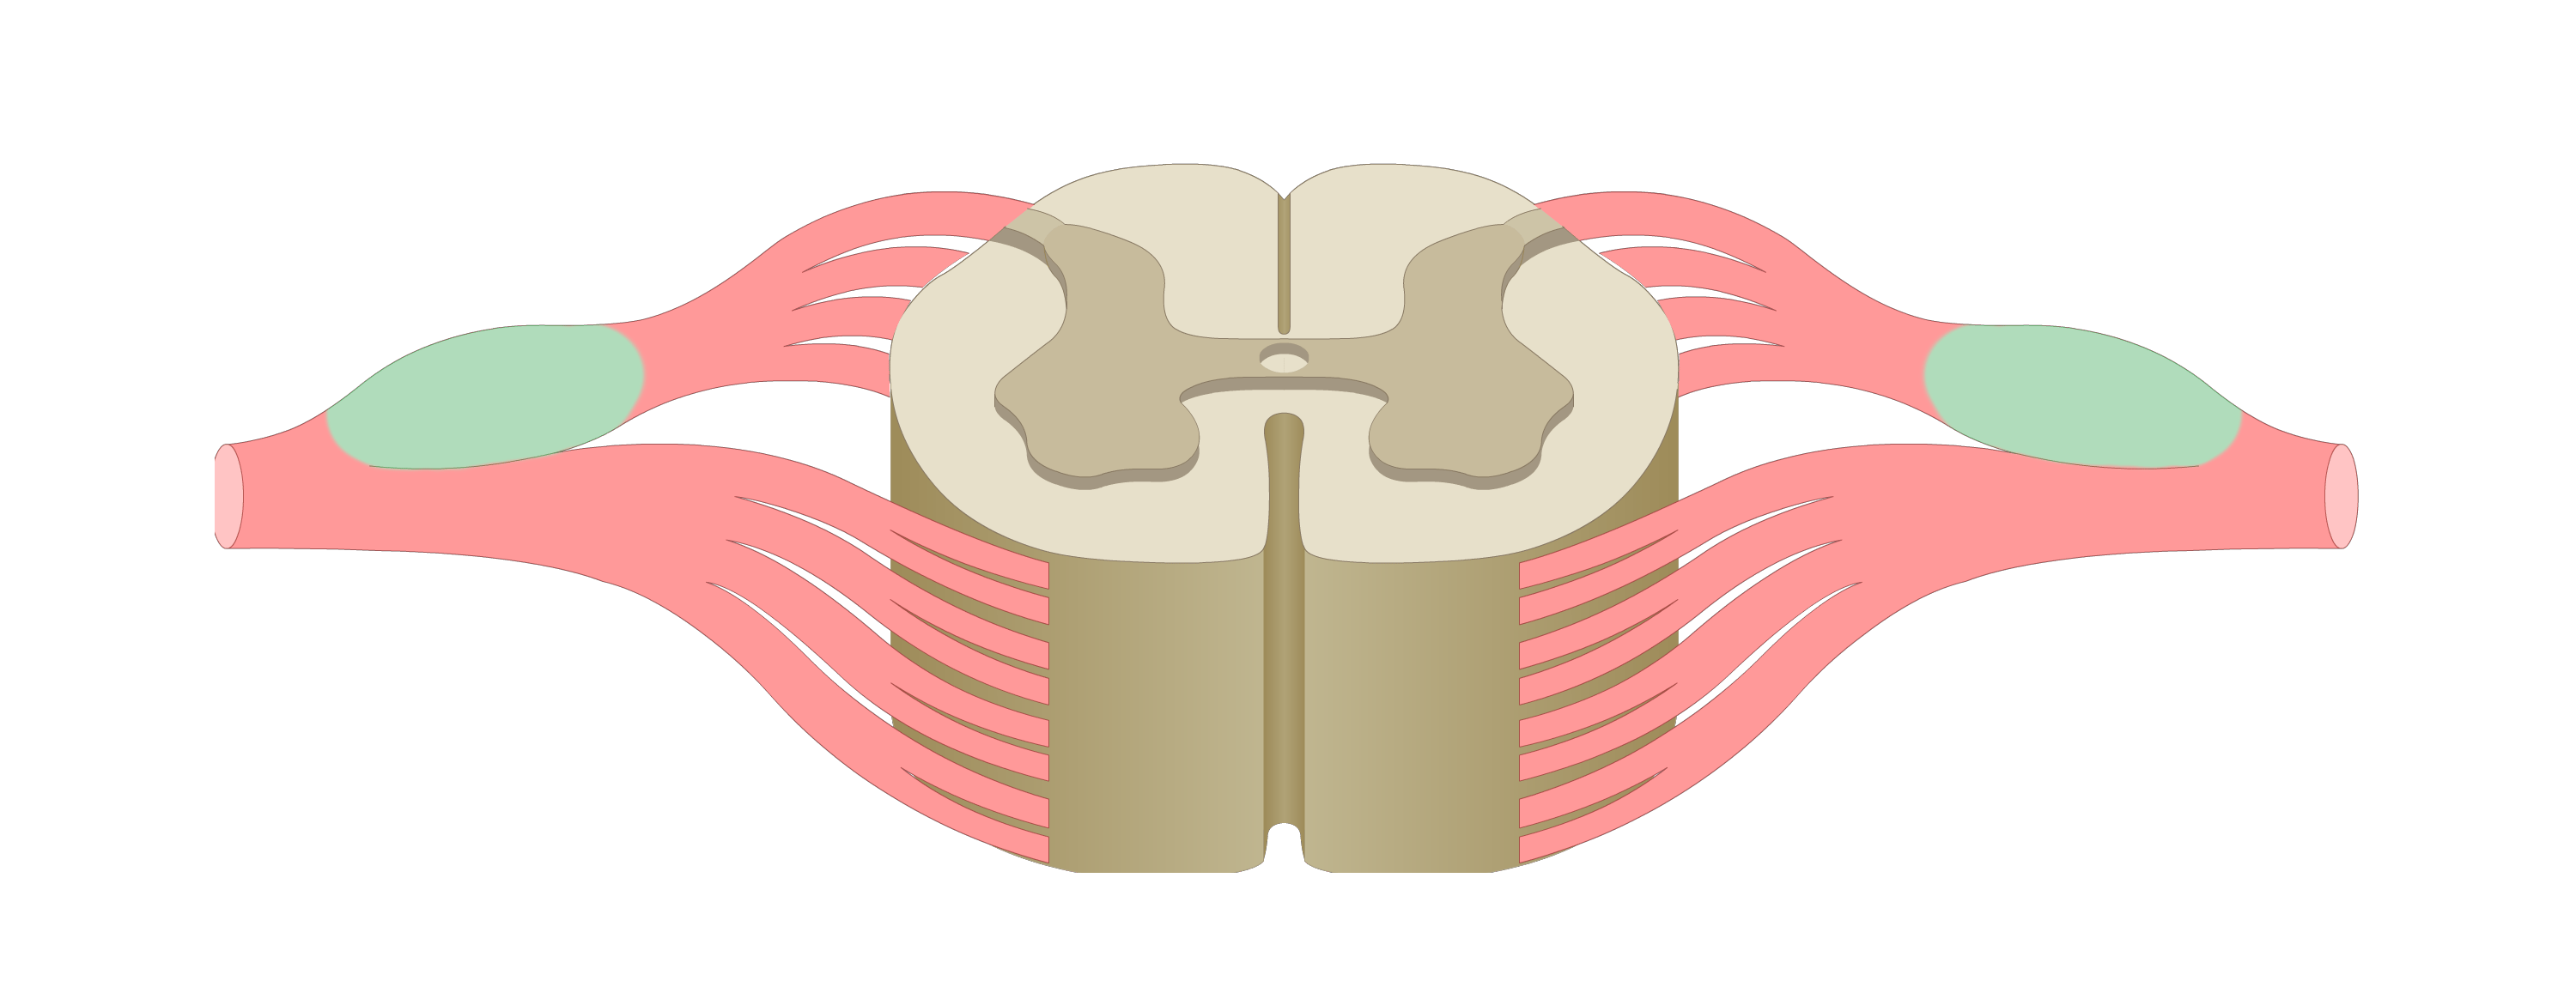

motor tracts

sensory tracts

dorsal root ganglion

dorsal horn

lateral horn

ventral horn

dorsal funiculus

lateral funiculus

ventral funiculus

central canal

ventral median fissure

dorsal median sulcus